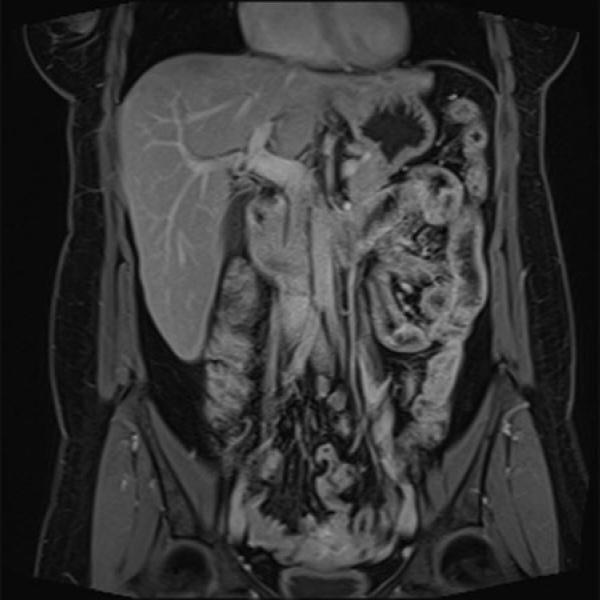

Resonancia nuclear magnetica de abdomen contrastado. EN. Codigo 883401C (2022)

Adicionalmente incluye al menos uno de los siguientes servicios: asesoría, orientación médica, consecución de la cita, acompañamiento, orientación geográfica, facturación, entrega de resultados.

ESCANOGRAFIA NEUROLOGICA S.A.

Medellin, Barrio Prado Centro: Calle 59 # 50 A - 14

Sabaneta, Carrera 48 # 50 sur 128. Al interior del Centro Comercial Mayorca Mega Plaza